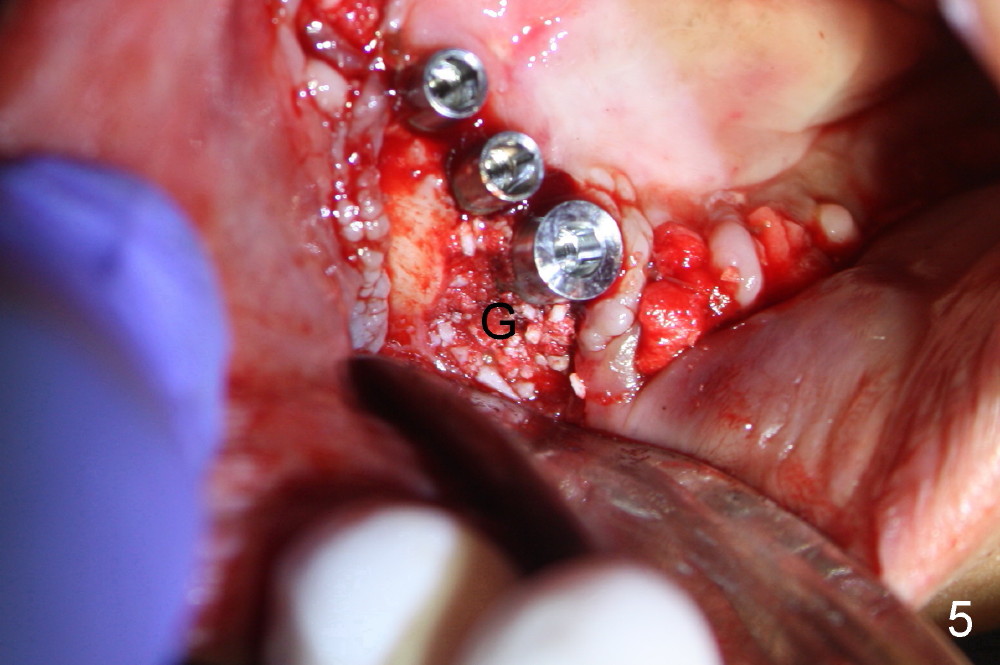

Osteotomy is initiated through the gingiva of the healing sockets at the sites of #22 and 27 (Fig.1) with difficulty (close surgery). The incisor crest incision is extended distal to the canine areas; an accessory oblique incision is supplemented to facilitate implantation (#22: 5x14 mm; #27: 4.5x17 mm) and expose the buccal defects (Fig.3,4, open surgery). The defects are grafted (Fig.5) and covered by collagen membrane (Fig.6). The incisions are closed and abutments are placed for immediate provisional (Fig.7).